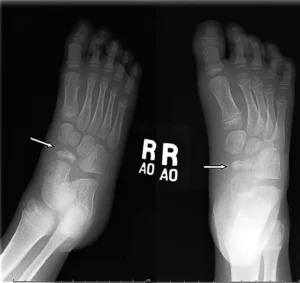

Hallux valgus (deformed thumb) is a condition in which the thumb of the foot is turned outwards, often with the formation of a painful squat. The most common causes are tight footwear, genetic predisposition and neuromuscular disorders. It can cause pain, swelling, walking problems and deformation of other fingers.